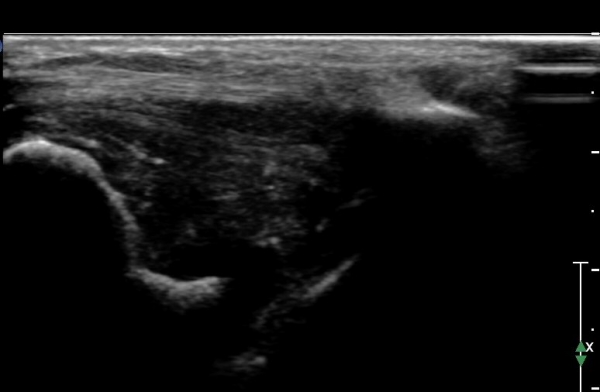

ÇϺΠ½ÅÀü ¶ì(inferior extensor retinaculum) ÀÇ frondiform Àδë Á¾´Ü¸é°Ë»ç¿¡¼­

frondiformÀδëÀÇ Àú¿¡ÄÚ ºÎÁ¾°ú °Å°ñÇÏ °üÀý °£°ÝÀÌ ¹ú¾îÁ® ÀÖ´Ù(»çÁø 8, 9).